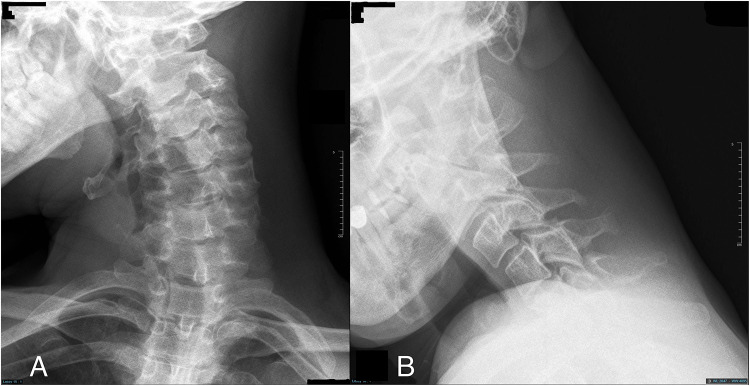

Introduction: Dystonia is a prevalent movement disorder characterized by involuntary muscle contractions, and cervical dystonia is among the most common forms. This report presents a rare case of severe isolated cervical dystonia in a young male patient that progressed to type IV atlantoaxial rotatory subluxation, highlighting the clinical presentation and diagnostic challenges associated with this condition.

Case description: A 27-year-old male patient presented with abnormal head posture and severe cervical pain. Clinical examinations revealed severe cervical muscle spasms and a unique head posture, as if he was looking at the tip of his right shoulder. Radiological evaluation revealed a type IV atlantoaxial rotatory subluxation. Despite initial attempt of close reduction under anesthesia, recurrence of the subluxation occurred, and surgical intervention was necessary.